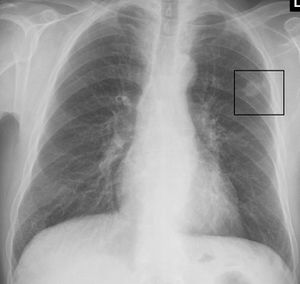

| أشعة مقطعية إكليلية تظهر سرطان كيس الرئة الخبيث. المفتاح: → ورم ←, ★ انصباب جنبي مركزي، 1&3 الرئتان، 2 العمود الفقري، 4 الضلوع، 5 الأورطى، 6 الطحال, 7&8 الكليتان، 9 الكبد.  | |